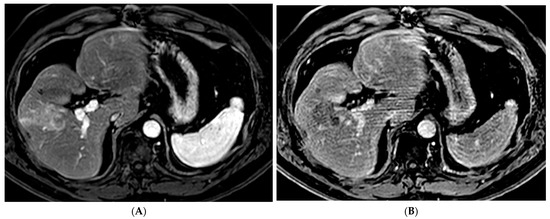

Figure 1.

66-year-old woman with cirrhosis secondary to autoimmune hepatitis and HCC, treated with microwave ablation. (A) Arterial phase MRI showing a 3.5 cm arterially enhancing mass in the periphery of segment 7. (B) Delayed phase MRI demonstrating washout of the mass. Intraprocedural axial (C) and coronal (D) CT images demonstrating probe placement bracketing the mass. (E) Arterial phase MRI one month post ablation showing no residual viable tumor. (F) Arterial phase MRI one year post ablation demonstrating no residual or recurrent viable tumor and involution of the ablation cavity.